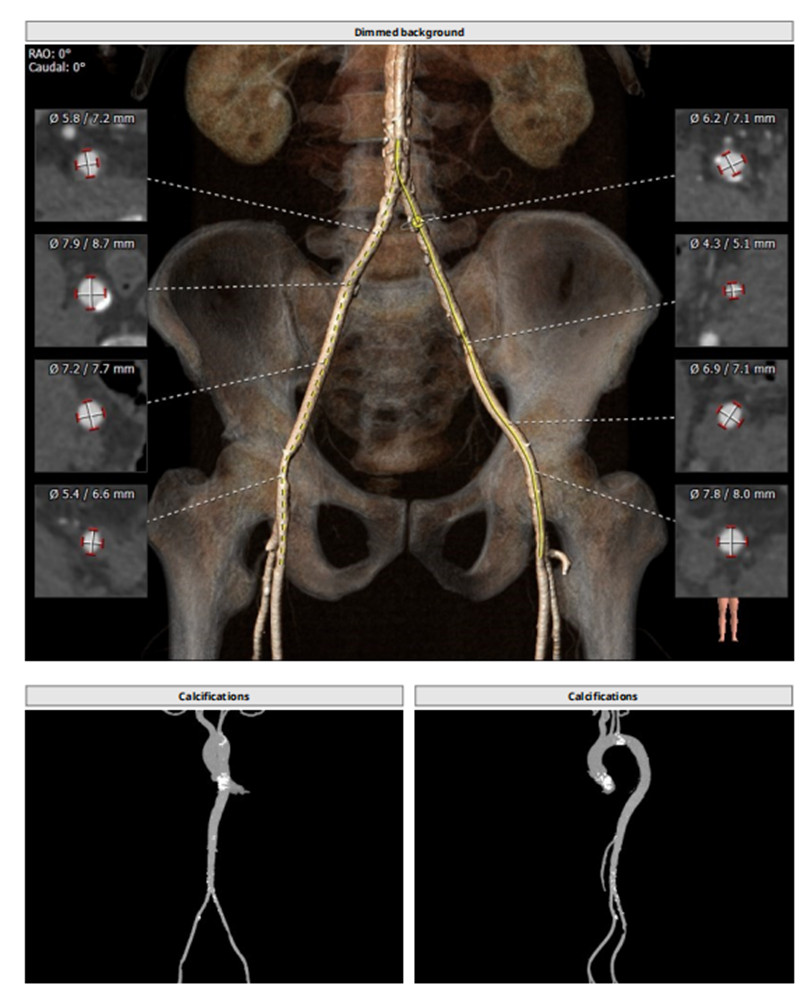

术前瓣膜结构评估

术前入路评估